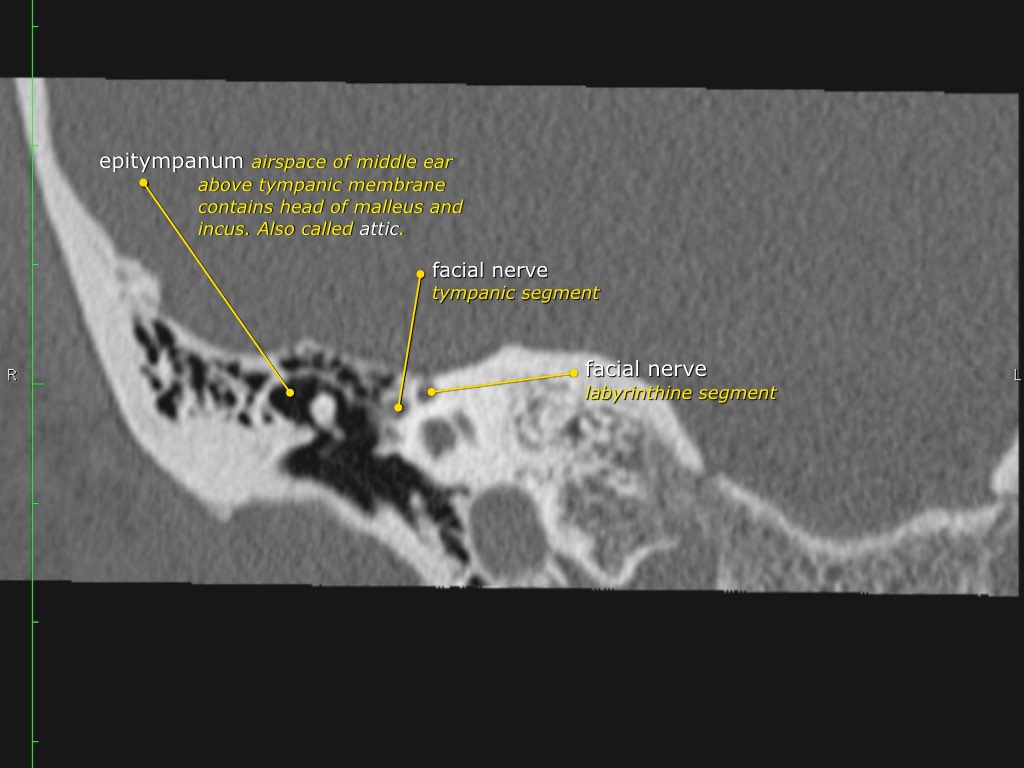

Đoạn mê nhĩ của dây thần kinh mặt xuất phát từ ống tai trong, chạy gần như vuông góc với trục dài của xương đá, gập góc nhọn về phía trước để đến hạch gối (geniculate ganglion).

Tại hạch gối, dây thần kinh mặt tạo thành một khúc quặt hình chữ U (genu thứ nhất của dây thần kinh mặt) để chạy ra phía sau theo đoạn nhĩ dọc theo thành trong của thượng nhĩ.

Trần

được gọi là tegmen, ngăn cách phần trên của hòm nhĩ (thượng nhĩ) với hố sọ giữa.

Hòm nhĩ

Hòm nhĩ là phần chính của tai giữa, chứa các xương con của tai giữa.